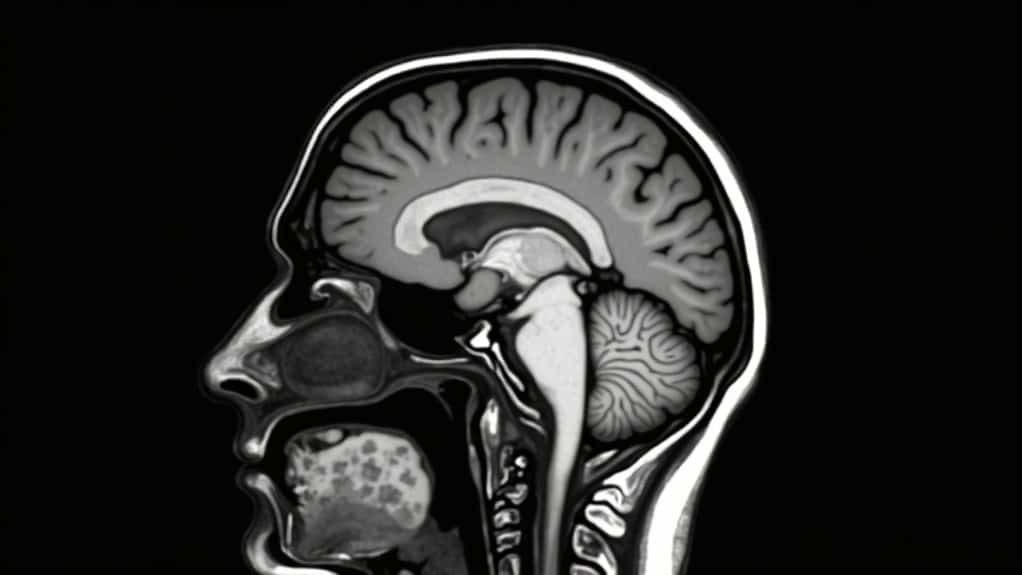

The brain has opioid receptors built into its reward center. When an opiate is taken or injected, this triggers the release of endorphins, known as the brain’s feel-good chemicals. This causes a sense of euphoria, pain relief, and deep relaxation, as if you have not a care in the world. The brain sends a signal that this feels good and should be repeated.

As repeated use of the drug continues, the brain will begin reducing the production of endorphins, which is a sign that tolerance is increasing. This often motivates someone to take higher doses than what is prescribed, or to dose at more frequent intervals.

Because the drug mimics natural brain chemicals, such as dopamine, the brain will stop producing dopamine, becoming dependent on the regular dosing of the drug. When the individual attempts to stop using the opiate, they will experience withdrawal symptoms within hours.